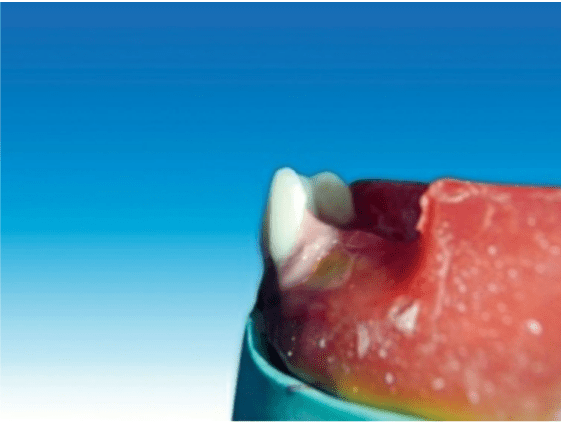

Placement of the maxillary central incisor in relation to all three planes.

🔻The long axis of the central incisor (the blue line) is positioned parallel to the

vertical axis (the red line) when viewed from the front

🔻The incisal edge of the maxillary central incisor is positioned in line with the

anterior occlusal plane . The central pin of the articulator will point the mesioincisal line edge of the central incisor.

🔻The central pin of the articulator will

point the mesioincisal line edge of the central incisor.

When viewed from:

Front: Long axis parallel towards the vertical axis.

Side: Slopes labially about 15 degrees.

Occlusal plane: Incisal edge is in contact with occlusal plane